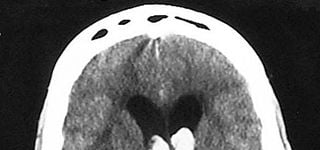

Identify the hemorrhage.